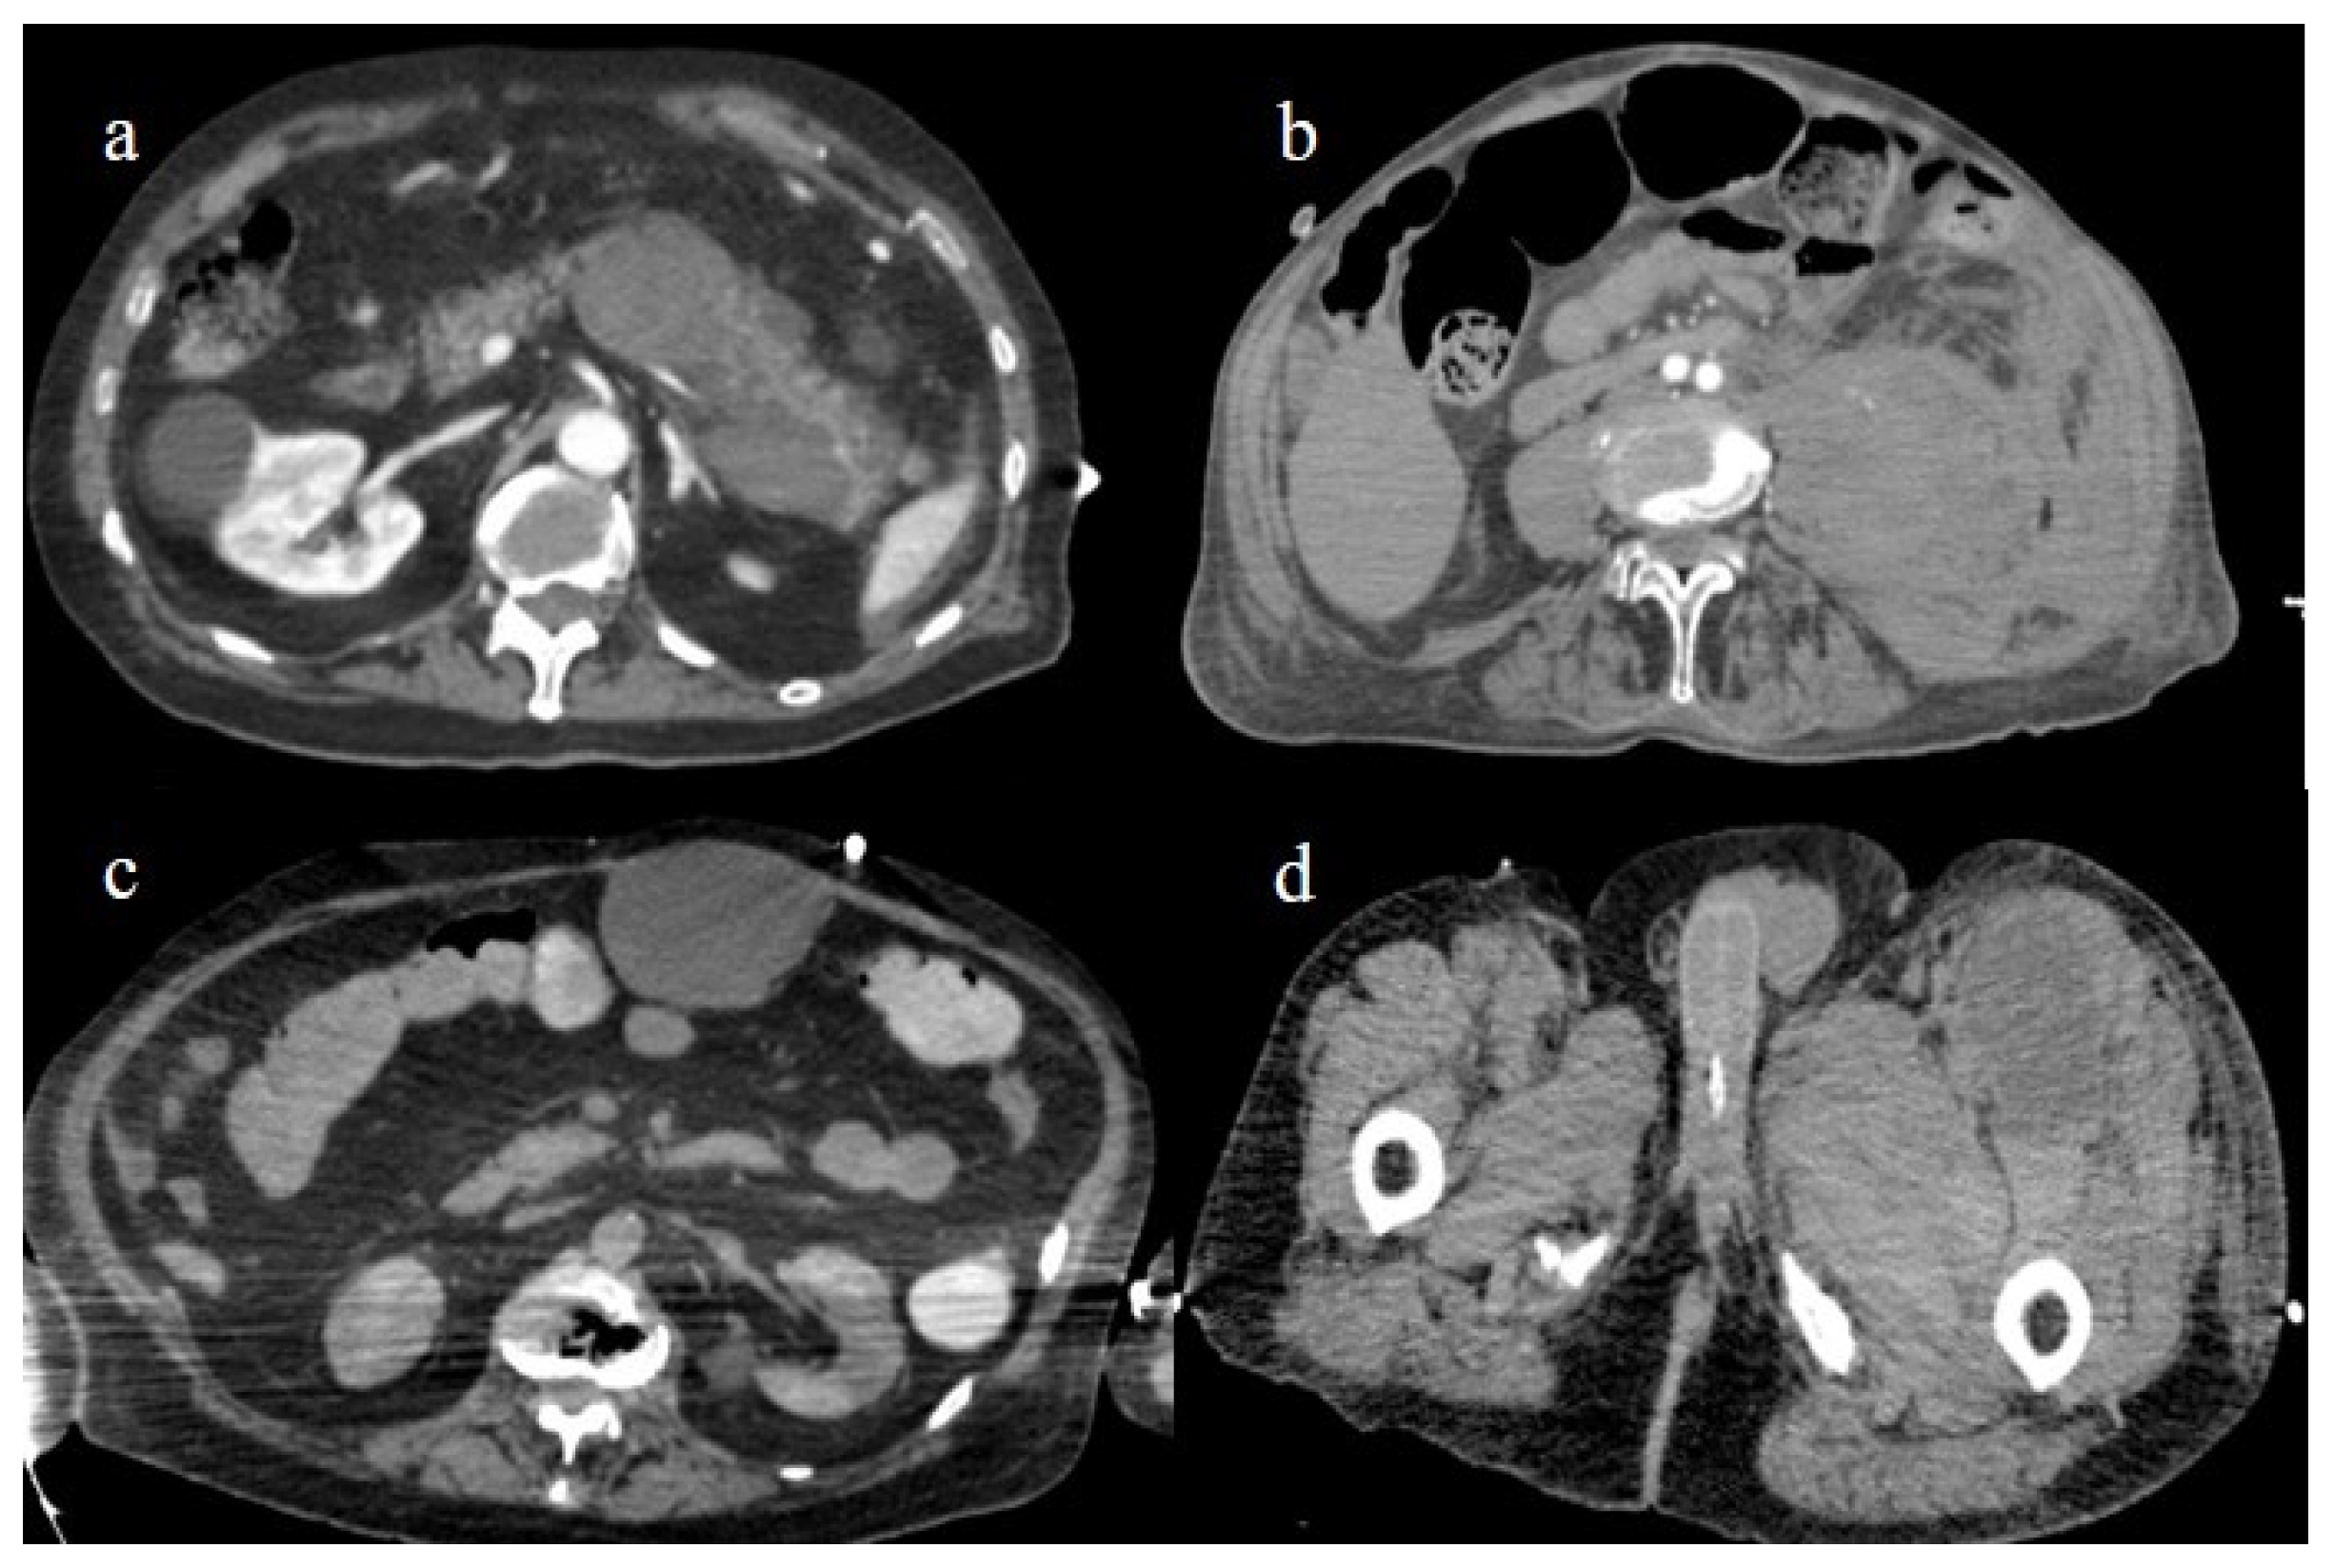

Figure 24.

The enhanced computed tomography of an 80-year-old patient during the second pandemic wave (December 2020) with the findings in image (a) of diffuse colic thickness with target appearance and some hemorrhagic changes compatible with ischemic colitis; in image (b), a large ischemic area of the spleen is also present.

4.2. Splenic and Renal Infarction

Splenic and renal infarction are rare ischemic abdominal complications in COVID-19 patients and have only been presented in case reports and a few case series [147,149,171,172,173,174,175,176,177,178,179]. Splenic and renal infarctions generally have a minor clinical impact compared to intestinal infarction. In very few cases, associations between these complications have been reported [147,180,181,182,183], and in some rare cases these were the first manifestations of a COVID-19 infection [171,177]. These complications are usually secondary to the state of hypercoagulability in COVID-19 infection that leads to an increased risk of arterial and venous thrombosis and thromboembolic events (Figure 24 and Figure 25).

Figure 25.

Enhanced computed tomography of an 80-year-old patient during the second pandemic wave showing an ischemic lesion of the spleen in image (a) (yellow arrow); the patient also had a large hematoma in the left psoas muscle, depicted in image (b) (orange arrow).

Figure 27.

Enhanced computed tomography during the first and second pandemic waves, showing in image (a) a retroperitoneal hemorrhage involving the pancreas; in image (b) a large hematoma of the left psoas muscle; in image (c) hematoma of the rectus abdomins; and in image (d) a depiction of a hematoma in the muscles in the left thigh.

In most cases, patients were older, receiving a prophylactic dose of subcutaneous enoxaparin, and showed moderate-to-severe COVID-19 pneumonia. Evrev et al. [152] reported 11 cases of spontaneous abdominal and gastrointestinal bleeding in hospitalized COVID-19 patients, with a male predominance and an average age of 74 years. In nine patients, the retroperitoneal and gastrointestinal bleeding complications followed anticoagulant treatment and were associated with pneumonia severity. Rare cases of gastrointestinal bleeding were also reported during the Omicron wave and were related to the colon [156]. All vascular abdominal complications are summarized in Table 3.